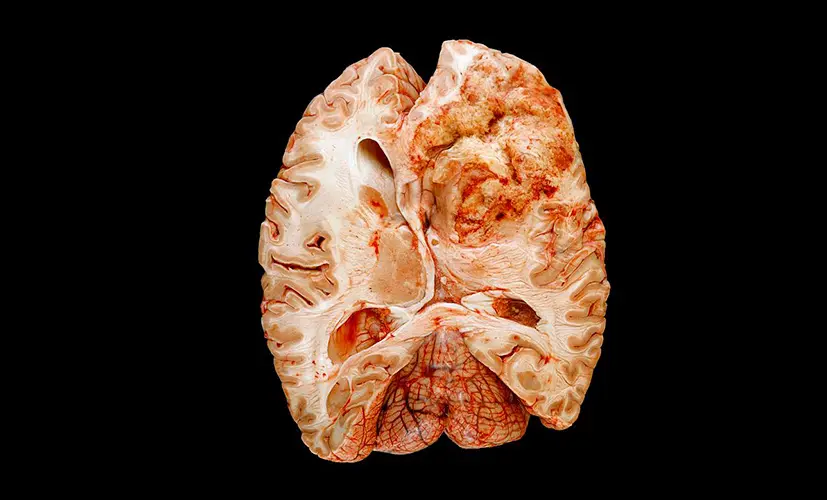

1.Complete memory loss - a life without clarity

The neural pathways in the brain become so damaged that no supplement can help. The person permanently loses their ability to recall memories. Relationships deteriorate. Confidence shatters. Depression takes hold. I've seen patients who isolated themselves at home, unable to face their loved ones.

2. Dementia - the silent thief

Untreated cognitive decline can evolve into dementia. It may start as occasional forgetfulness, but before you know it, the condition has spread, impairing judgment and daily function. Patients describe the mental haze as a fog they can't escape. Most are diagnosed too late-when little more can be done.

3. Brain fog leading to chronic fatigue

Inflammation spreads from the brain to affect overall neurological health. The result? A mind that slowly shuts down. Mental exhaustion becomes your new norm-struggling to think clearly, day after day, as your body weakens. I've seen individuals beg for relief that never arrives.